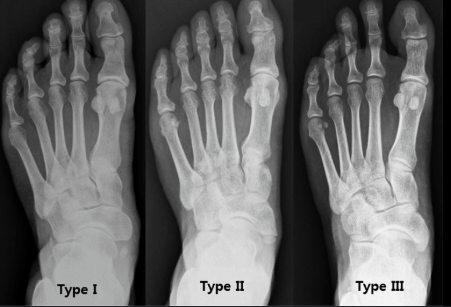

♼ 분류

유형 | 설명 | 특징 및 임상적 의미 |

제1형 | 주상골과 완전히 분리된 부주상골로,크기가 작은 | 증상이 경미하며 대부분 문제 없이 지냄 |

제2형 | 주상골과 부주상골이 반쯤 붙어 있어 덜렁거리는 상태 | 가장 문제되는 유형으로, 심한 통증과 기능장애를 유발하며 골절과 감별 필요 |

제3형 | 부주상골이 주상골의 일부로 융합되어 뼈가 크게 형성된 경우 | 경미한 증상이나 드물게 부주상골에 의한 문제가능 |

이 중 제2형이 부주상골 증후군 환자에서 가장 흔히 문제를 일으키는 유형이며, 인대와 근육 비정상 발달이 동반되어 수술적 치료가 고려되는 경우가 많습니다. 반면 제1형과 제3형은 증상이 경미하거나 거의 없어서 일상생활에 큰 지장이 없습니다